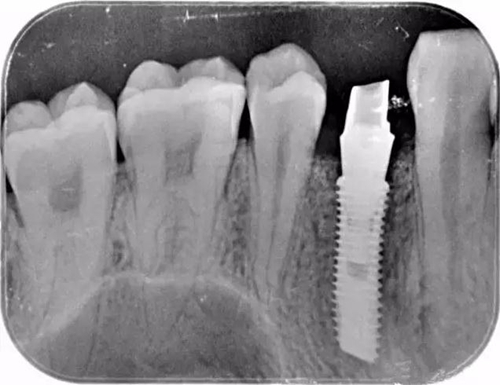

該顧客選擇的是登騰Superline種植體.因為顧客骨高骨寬條件很好,選擇種植4.0*12植體植入。術中發(fā)現(xiàn)頰側骨壁存在缺損,植入Biooss骨粉,加固種植體。從照片中可以看到基臺愈合之后的效果不錯。

這個是顧客術后旋入成品基臺的X片